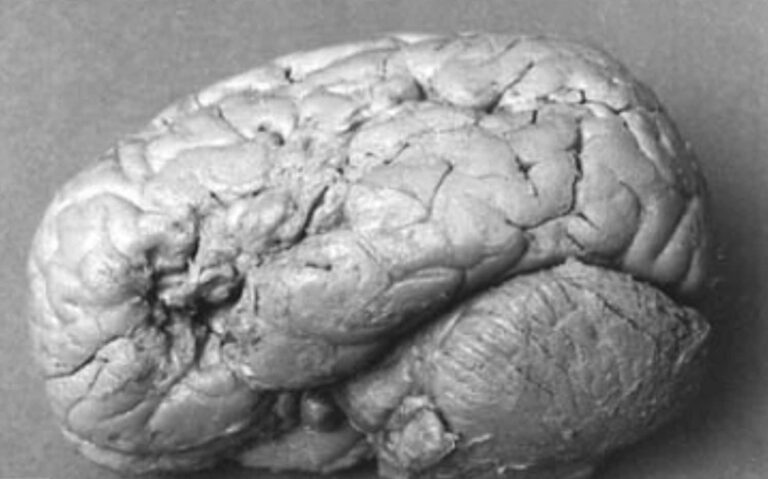

cervello paziente tan tan

Det kliniske tilfellet med «pasientbrun», mannen med Brocas afasi som bare gjentok disse to ordene

Mellom 1841 og 1861, året for hans død, fransk Louis Victor Leborne Han kunne bare